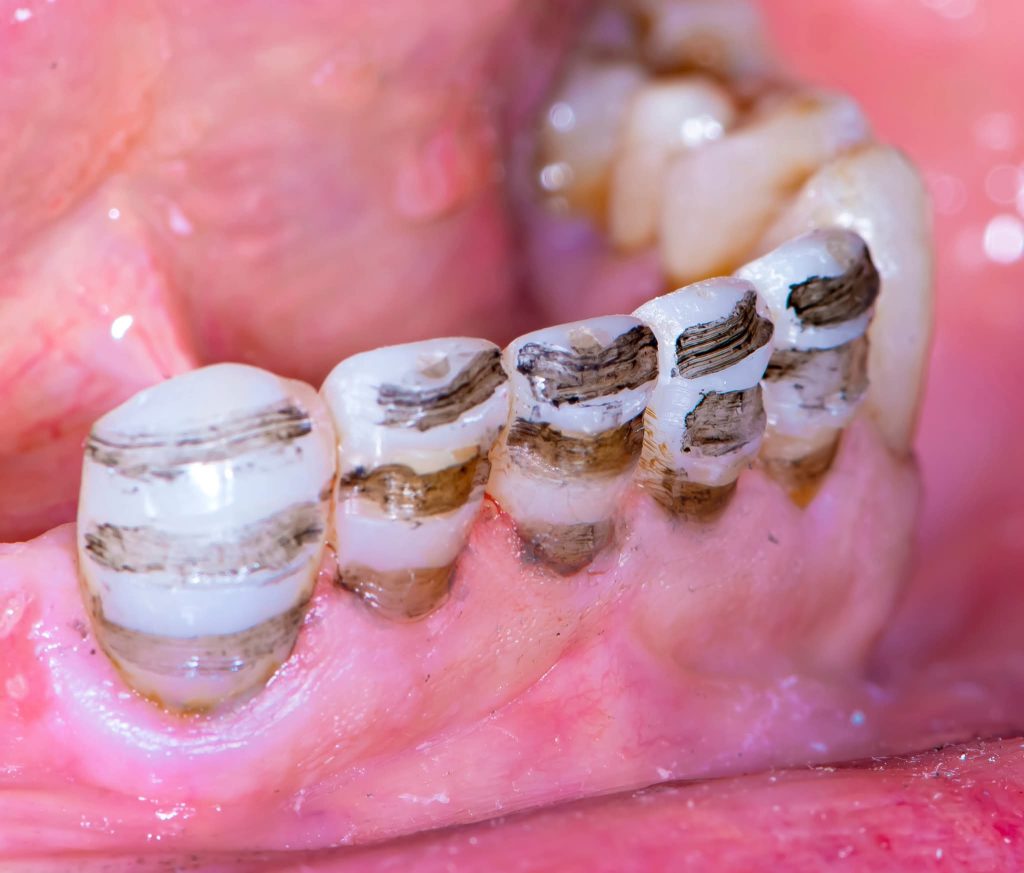

2. Corrective Phase:

This phase included all necessary corrective procedures:

Extraction of hopeless teeth.

Endodontic treatments.

Replacement of old, defective fillings.

Tooth build-ups to the new vertical dimension of occlusion, aided by the silicone indices.

Removable prostheses were inserted, and the patient was monitored for one month.

Minor occlusal adjustments were made during this period to achieve a more stable, comfortable occlusion and proper phonetics.